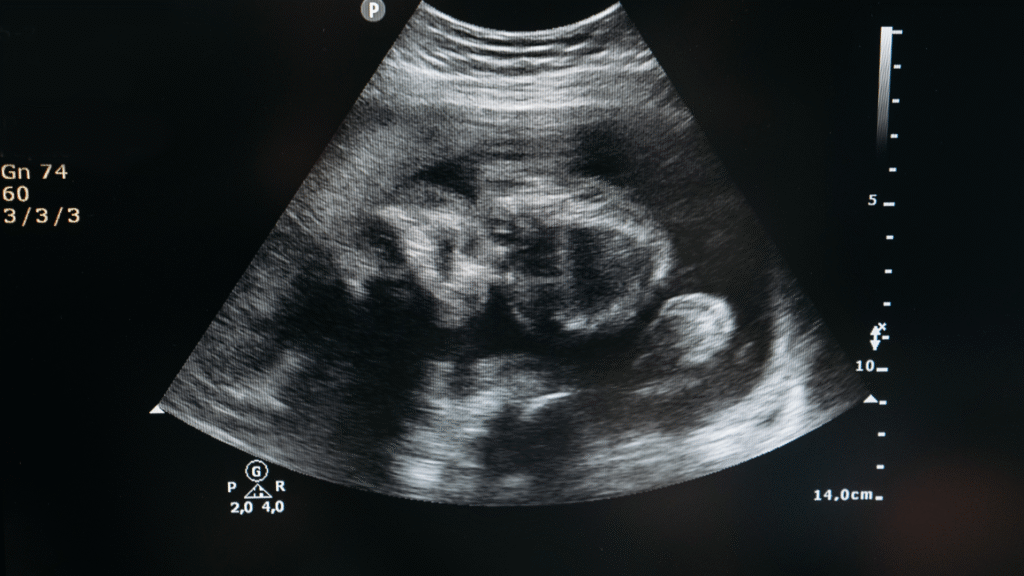

O ultrassom morfológico do 1º trimestre é um exame fundamental, realizado entre 11 semanas e 13 semanas + 6 dias de gestação. Ele marca um momento crucial do pré-natal, pois permite avaliar de forma precoce a formação inicial do bebê e estimar o risco de alterações genéticas.

Esse exame não só avalia se o bebê está se desenvolvendo bem nas primeiras semanas, como também identifica fatores de risco para síndromes genéticas, alterações cardíacas e más-formações estruturais. Ele permite, quando necessário, o encaminhamento precoce para testes complementares, como o teste genético não invasivo (NIPT) ou a biópsia de vilo corial.